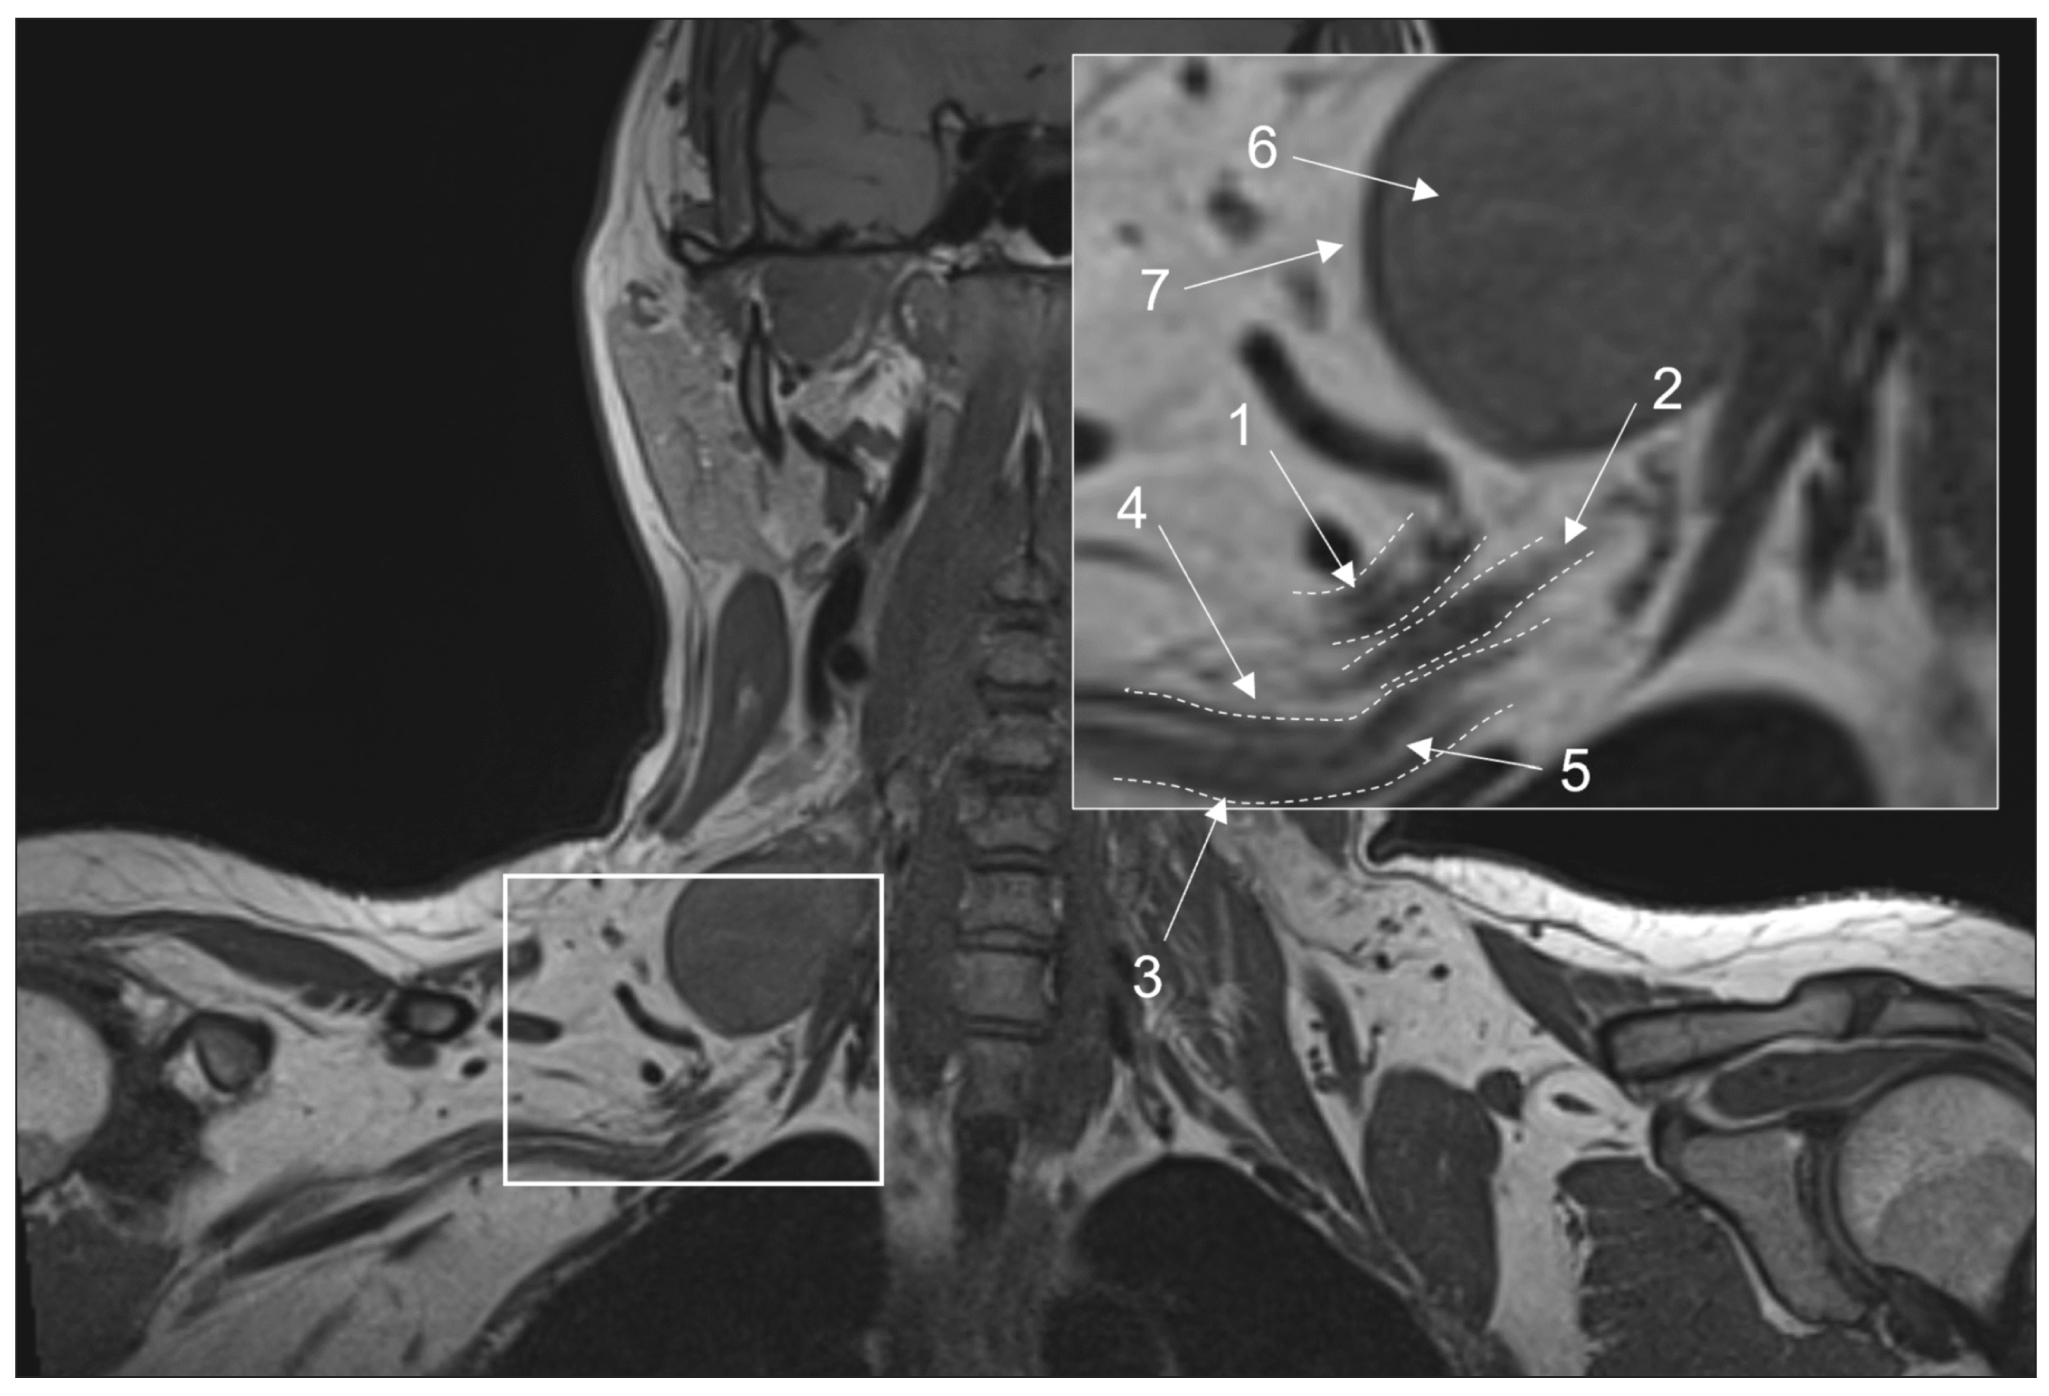

周围神经病是最常见的神经系统疾病之一。虽然已经有了完善的辅助仪器诊断方法,如神经肌电描记术和超声检查,但对各种原因引起的周围神经损坏,尤其是其近端损坏的诊断和鉴别诊断仍很困难。目前,外周神经的磁共振成像已被积极引入临床实践,成为一种宝贵的辅助诊断工具。

本文重点介绍上述检查方法的主要优点和局限性、使用磁共振成像来显示出周围神经系统结构的历史、考虑到现代技术能力的不同定位周围神经磁共振成像协议书的主要要求,包括对标准检查中使用的磁共振成像序列及其诊断价值、使用造影剂的建议以及各种脂肪抑制机制的优缺点的详细讨论。